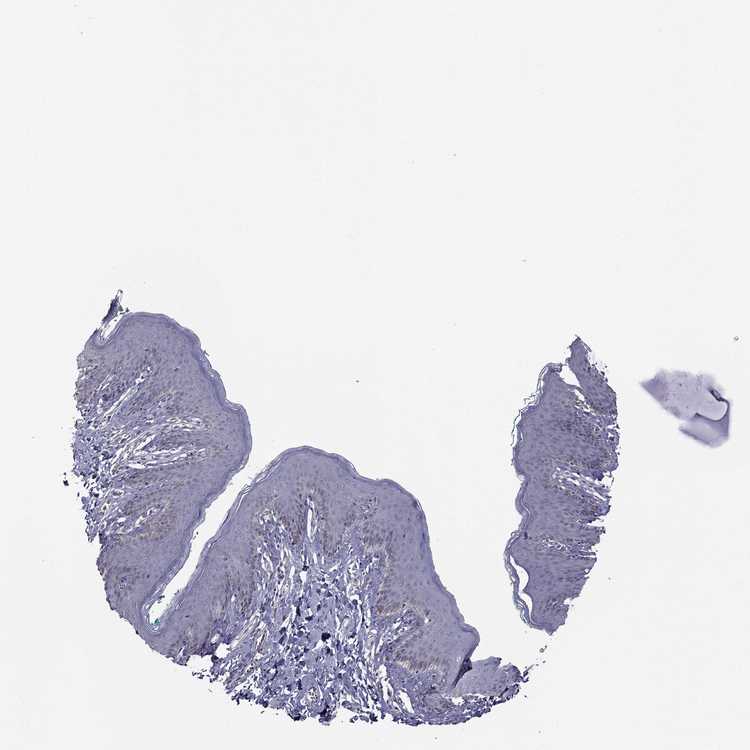

SKIN 2 - Antibody stainingi

Antibody staining in the annotated cell types in the current human tissue is reported as not detected, low, medium, or high, based on conventional immunohistochemistry profiling in selected tissues. This score is based on the combination of the staining intensity and fraction of stained cells.

Each image is clickable and will lead to virtual microscopy that enables deeper exploration of all samples and also displays staining intensity scores, fraction scores and subcellular localization as well as patient and tissue information for each sample.

Antibody HPA022974

Epidermal cells Not detected